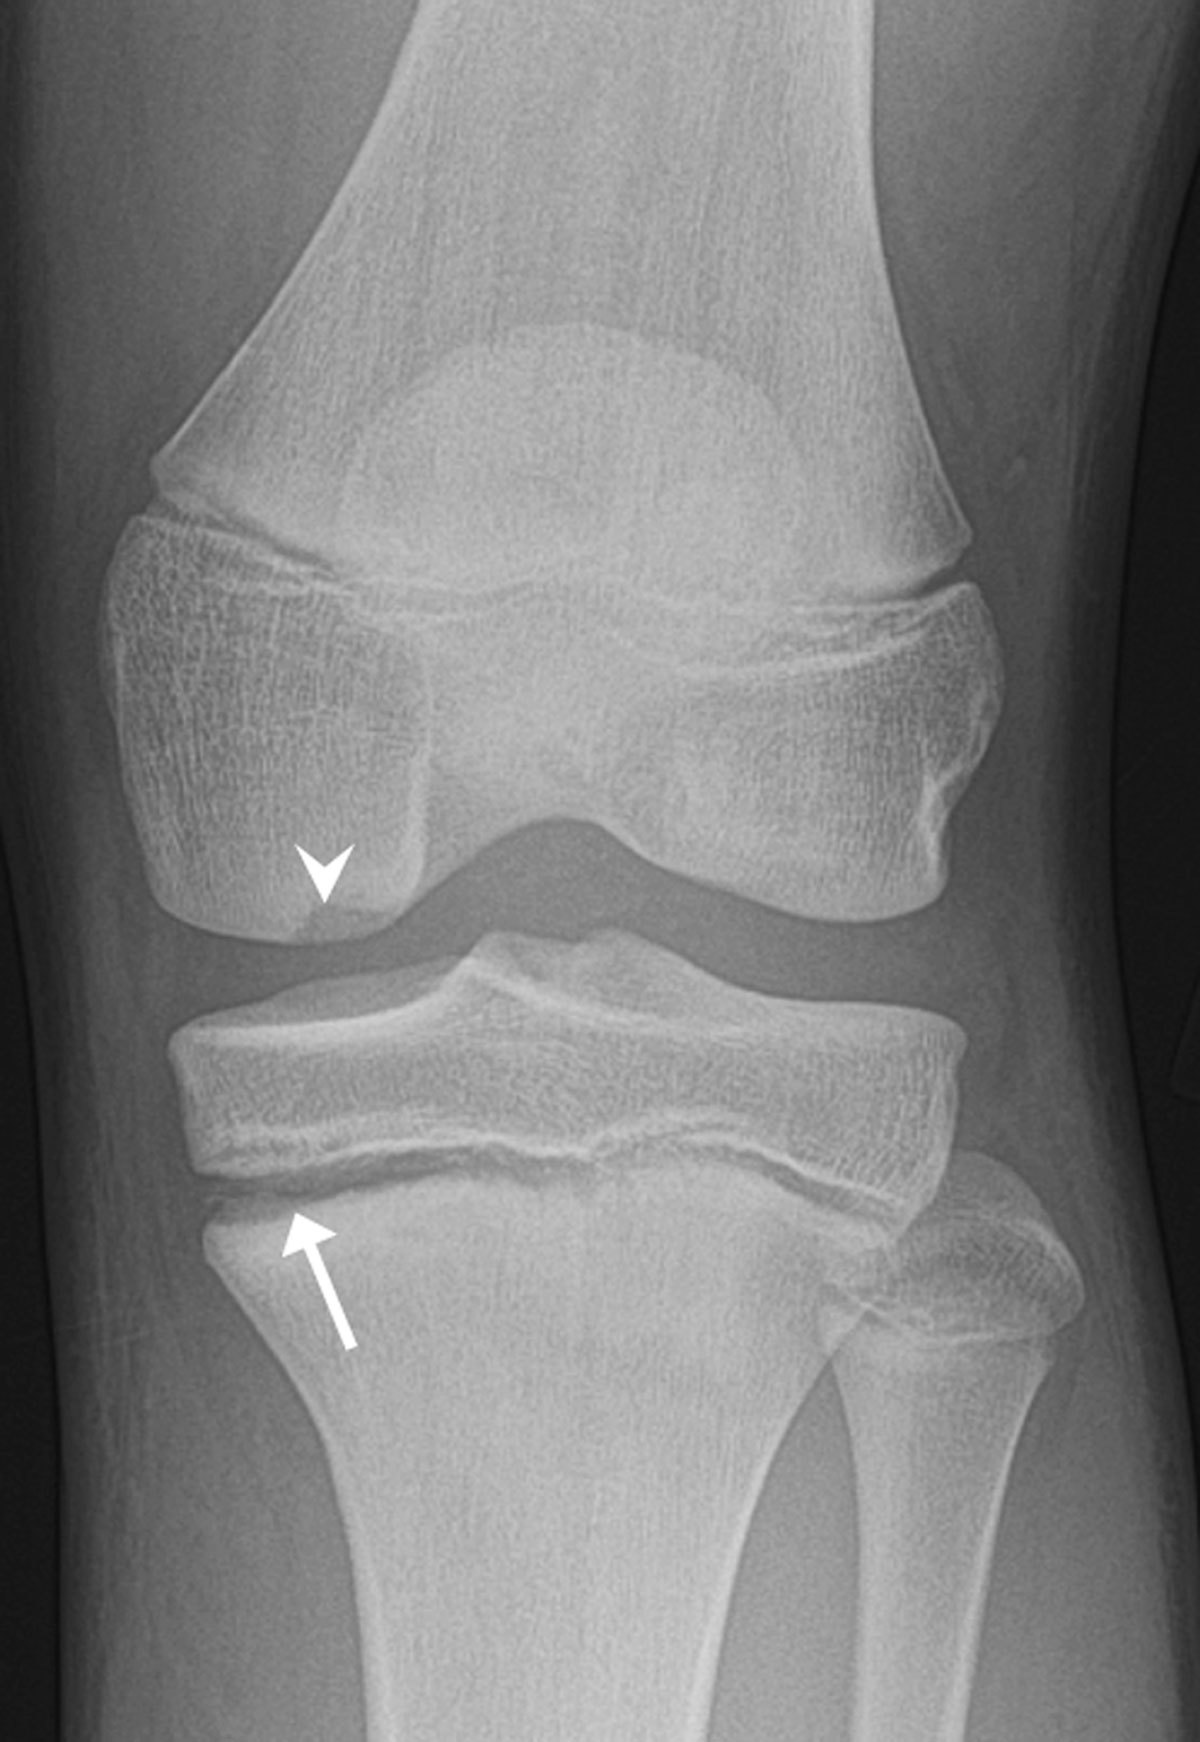

Fractura impactata - frecvent intalnita in

A

osul metafizar

fracturi col femural

extremitate distala radiala

platou tibial